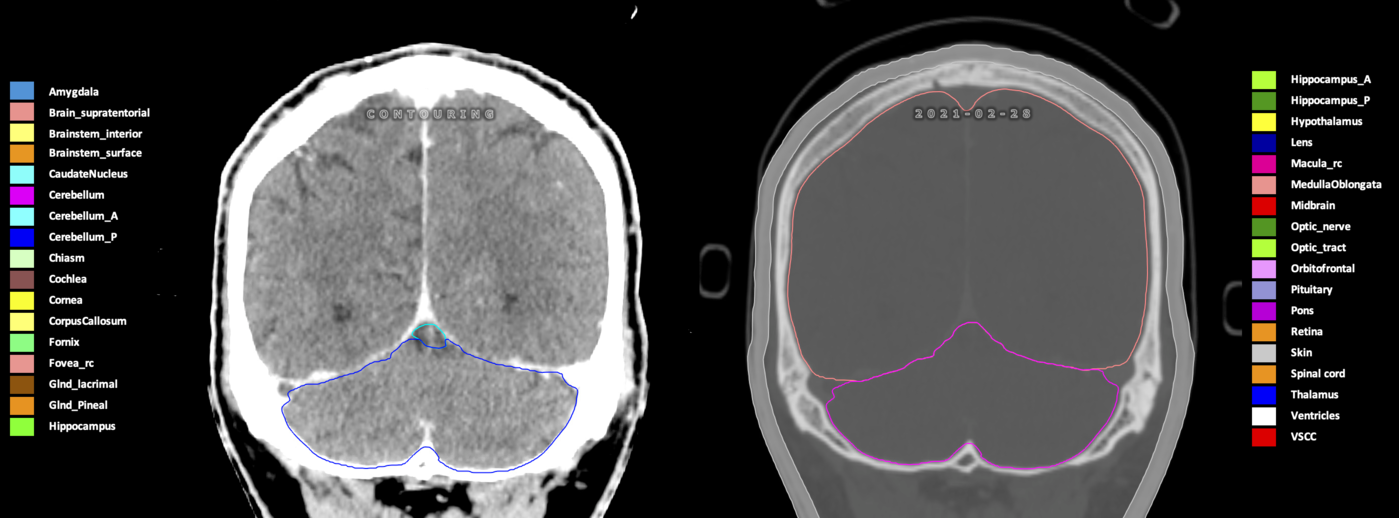

Eekers et al. have published an international neurological atlas for contouring of organs at risk in consensus with the European Particle Therapy Network (EPTN) in 2018 and an update in 2021. The purpose of this consensus atlas is to decrease inter- and intra-observer variability in delineating OARs relevant for neuro-oncology.

Included are all OARs known to be relevant for radiation-induced toxicity in neuro-oncology: brain, brainstem (midbrain, pons, medulla oblongata), chiasm, cerebellum (anterior & posterior), cochlea, cornea, hippocampus (anterior & posterior), hypothalamus, lens, lacrimal gland, optic nerve, pituitary, skin, and vestibular & semicircular canals. To further facilitate research on cognition, vision and radiological changes after irradiation of the brain, potential clinically-relevant OARs are included: amygdala, caudate nucleus, cerebellum (anterior & posterior), corpus callosum, fornix, macula, optic tract, orbitofrontal cortex, periventricular space (PVS), pineal gland, and thalamus.

Three-dimensional delineation of the 25 consensus OARs for neuro-oncology are shown on CT (WW/WL 120/40, 3000/600), 3T MR images, (T1Gd, T2FLAIR 1mm) and 7T MR (MP2RAGE 0.7 mm). All are presented in transversal, sagittal and coronal view.